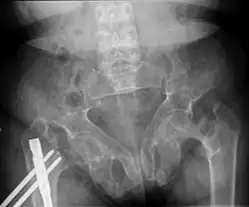

Brown tumors in the pelvis and a hip fracture.[18] -

Subchondral resorption in the sacroiliac joint.[18] -

Renal osteodystrophy is usually diagnosed after treatment for end-stage kidney disease begins; however the CKD-MBD starts early in the course of CKD.[1][6] In advanced stages, blood tests will indicate decreased calcium and calcitriol (vitamin D) and increased phosphate, and parathyroid hormone levels. In earlier stages, serum calcium, phosphate levels are normal at the expense of high parathyroid hormone and fibroblast growth factor-23 levels. X-rays will also show bone features of renal osteodystrophy (subperiostic bone resorption, chondrocalcinosis at the knees and pubic symphysis, osteopenia and bone fractures) but may be difficult to differentiate from other conditions. Since the diagnosis of these bone abnormalities cannot be obtained correctly by clinical, biochemical, and imaging methods (including measurement of bone-mineral density), bone biopsy has been, and still remains, the gold standard analysis for assessing the exact type of renal osteodystrophy.[6][16]